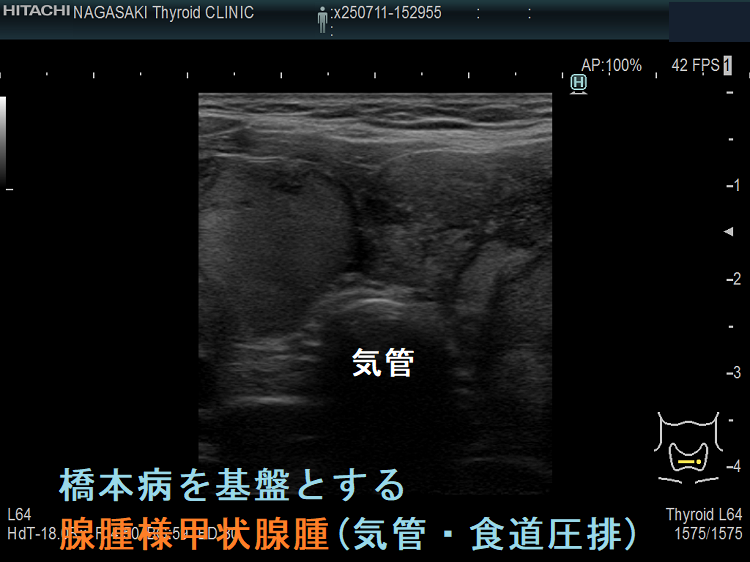

ケース④ 橋本病を基盤とする腺腫様甲状腺腫(気管・食道圧排)

橋本病を基盤とする腺腫様甲状腺腫(気管・食道圧排) 矢状断;等エコーなので甲状腺悪性リンパ腫が隠れているようには見えないが、潜在性甲状腺癌(甲状腺ラテント癌)が存在する可能性は否定できない。かなり気道圧迫している。